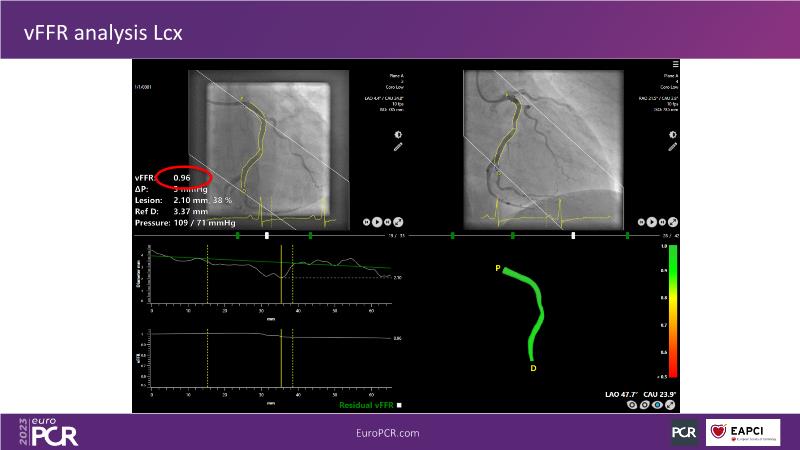

Explore angiography-based FFR/virtual FFR in this session. Uncover clinical evidence, identify ideal patients, and learn step-by-step integration into daily practice.

• To know the clinical evidence behind angiography-based FFR/vFFR

• To learn step by step how to apply it in your daily practice